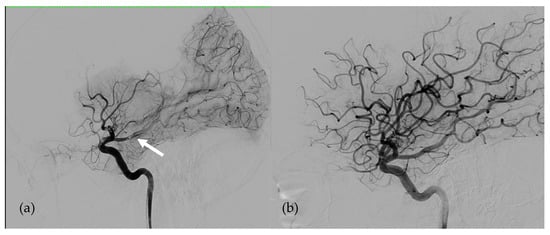

Figure 2. Angiographies of Right Internal Carotid Artery in patient 2. (a) Right Middle Cerebral Artery occlusion responsible for left hemiplegia just before revascularization (the white arrow shows the thrombus). (b)Early after endovascular revascularization by mechanical thrombectomy 70 min after the onset of the symptoms.

Despite these adjustments, the patient suffered an embolic stroke on the 56th day of assistance related to an acute occlusion of the bifurcation of the right proximal middle cerebral artery responsible for left hemiplegia. In the month prior to the stroke, the anti-Xa activity was between 0.30 and 0.55 IU/mL. At this time, relay by anti-vitamin K treatment was not initiated because unfractionated heparin was easier to manage in this patient’s context. The early in-hospital diagnosis of the neurological deficit allowed treatment by mechanical thrombectomy with a combined stent retriever and aspiration catheter technique 70 min from the onset of symptoms with no bleeding complication. Therapeutic anticoagulation and platelet anti-aggregation were continued without any modification in the immediate pre- and post-interventional periods. Revascularization of the right middle cerebral artery allowed the neurological deficit to immediately be corrected. Subsequently, the patient made a complete recovery. After this episode, therapeutic anticoagulation and platelet anti-aggregation with acetylsalicylic acid were continued according to the same protocol.